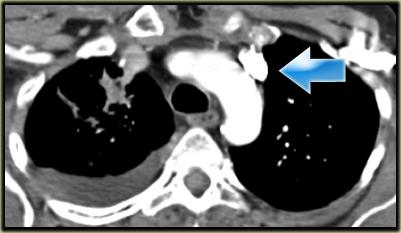

Describe the images on the left and then continue reading.

On the left side there is a vascular structure, that runs inferiorly below the level of the left hilum and enters into a dilated coronary sinus.

The diagnosis is left or double superior vena cava.

Left Superior Intercostal Vein.

This is an anastomosis between the accessory hemiazygos vein and the left brachiocephalic vein.

It courses along the lateral margin of the aortic arch (‘aortic nipple’).

It is a normal variant and if you look for this structure you will frequently notice it.

Notice the ‘aortic nipple sign’.